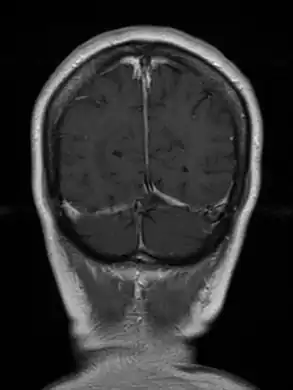

Cerebral toxoplasmosis (with primary involvement in the right occipital lobe) -

Cerebral toxoplasmosis -

Cerebral toxoplasmosis